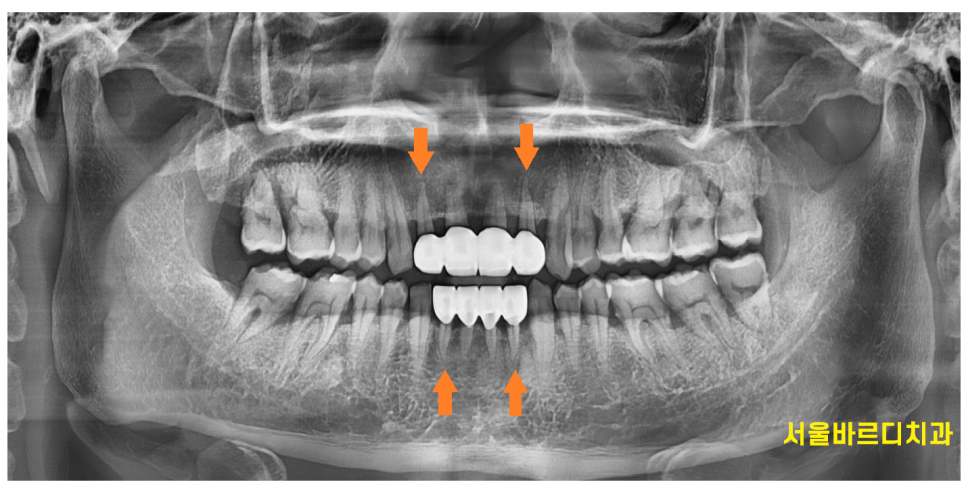

환자분도 전반적인 잇몸뼈 확인을 위하여 x ray를 찍어보았을 때

잇몸 뼈가 많이 내려간 상황이었습니다.

만성 치주염이 진행되고 있어

치아 사이 벌어진것을 치료하면서

잇몸 치료도 병행하셔야했습니다.

위아래 4개씩 치아를 삭제하여 공간을 재분배

파노라마상에서도 공간이 잘 메꿔졌습니다~